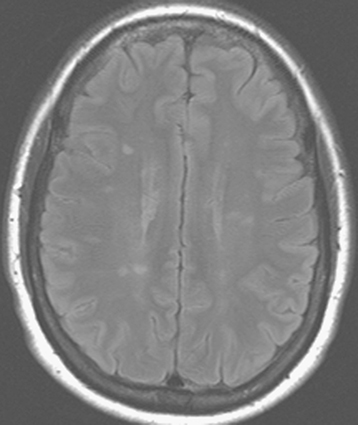

All patients with clinical signs or symptoms of optic neuritis from suspected demyelinating disease should undergo brain MRI with gadolinium. Fluid-attenuated inversion recovery (FLAIR) images are especially useful. See Figure 14.3.4 and 10.14, Optic Neuritis.